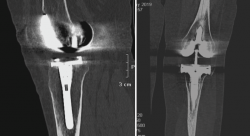

3. Artrosis

La gonartrosis es la causa más frecuente del dolor de rodilla después de los 50 años. En la radiografía se observa una reducción de la interlínea femorotibial o femoropatelar, y una osteofitosis marginal (Figura 6).

Figura 6. Radiografías anteroposterior y lateral de rodilla: osteofitos en compartimentos femorotibial y femoropatelar.